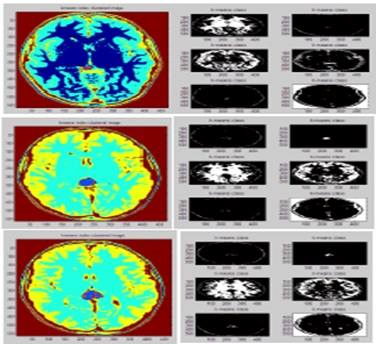

A study in the College of Science, University of Babylon on invention new method of creating three-dimensional images of MRI in detecting of brain tumors in order to gain more information In the anatomy of the flexible tissues in the human body and giving accurate details without any surgical interference or ionizing radiation.

The study included using digital image processing techniques based on the MRI replication pattern with the addition of some morphological processes to isolate and extract tumor from serial images of patients with tumors in the brain via generate 3D images.